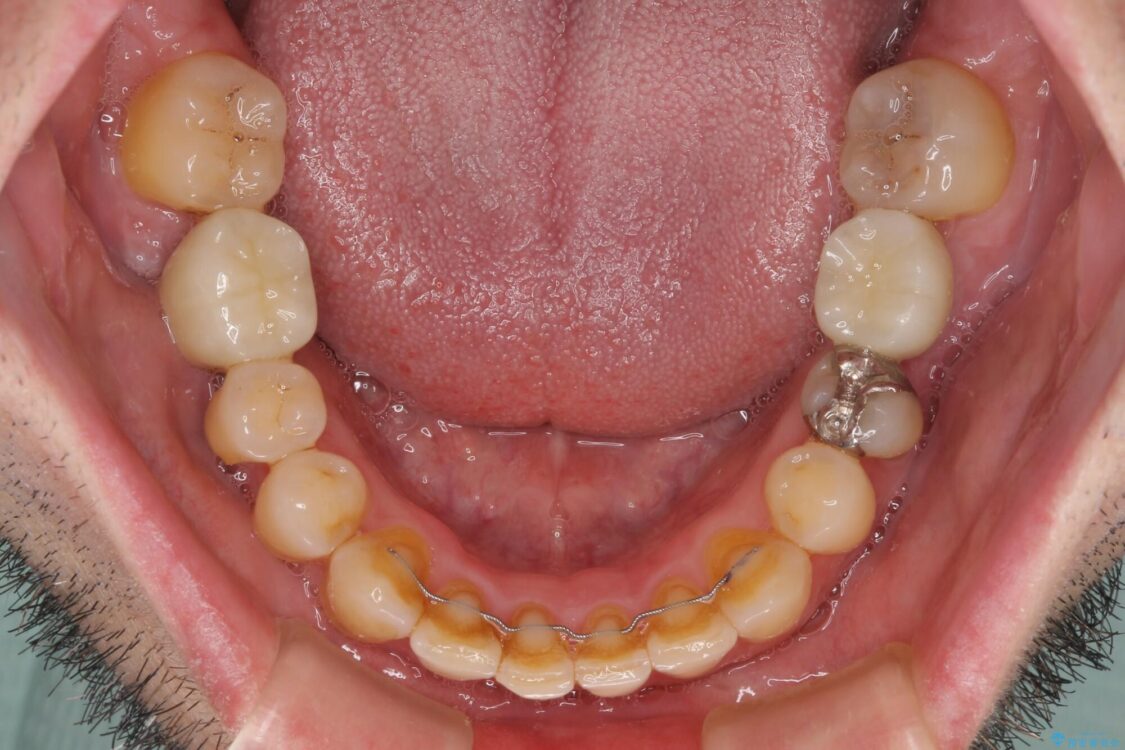

矯正治療でインプラント埋入を行い、矯正治療後に気になる前歯と合わせてオールセラミッククラウンによる補綴治療を行うこととしました。

治療途中

• 割れてしまった奥歯とデコボコの前歯 矯正治療とインプラント治療 治療途中画像